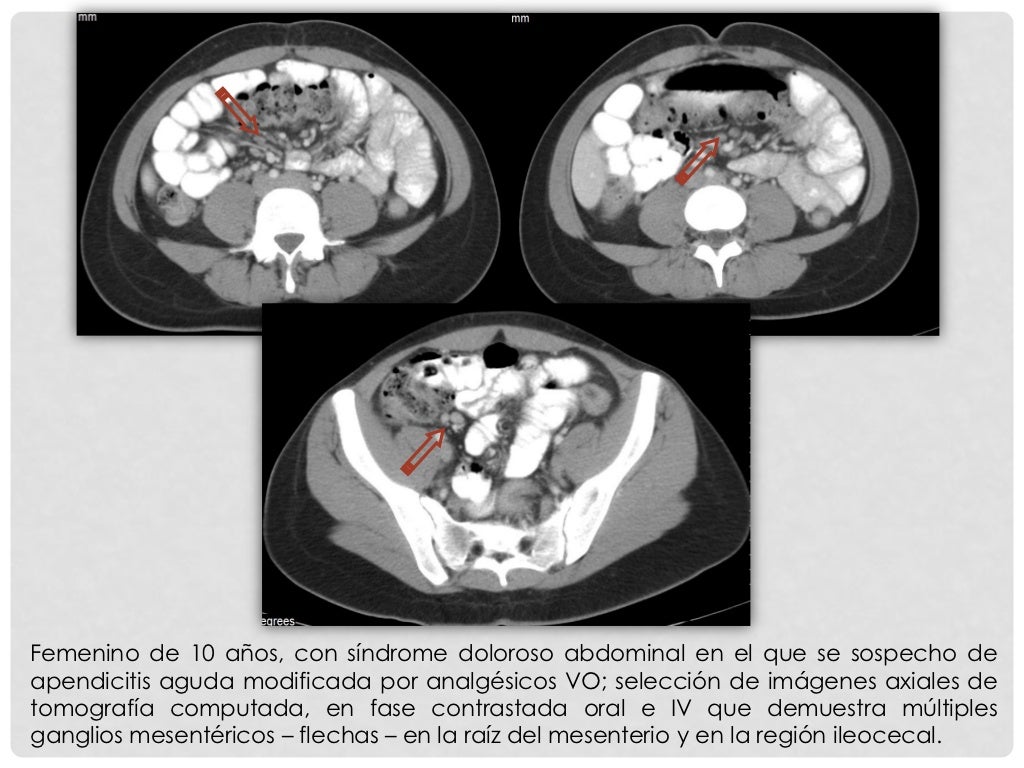

GASTROPEDIATRA EXPLICA SOBRE ADENITE MESENTÉRICA INFANTIL, ENTENDA O QUE É , CAUSAS E TRATAMENTO.#DORABDOMINALINFANTIL#ADENITEMESENTERICA1- compre o ebook so.. Mesenteric adenitis (rare plural: adenitides), less commonly called mesenteric lymphadenitis (rare plural: lymphadenitides), is a self-limiting inflammatory process that affects the mesenteric lymph nodes in the right lower quadrant and is clinically often thought initially to be acute appendicitis, a common diagnostic mimic.